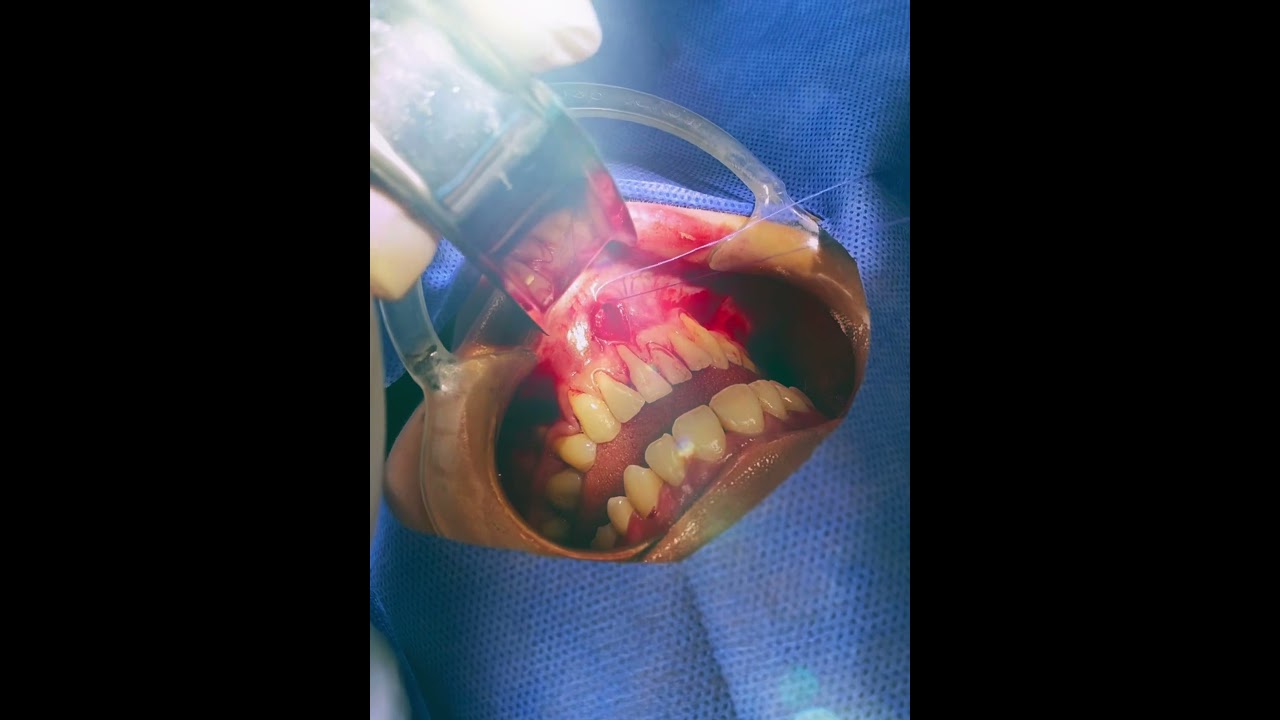

Exodoncias de cordales

Si eres nervioso para realizar tu cirugia de cordales hoy en día te ofrecemos la sedación consciente en el consultorio, vas a estar somnoliento y no sentirás tu cirugia, cuando despiertes ya tu procedimiento habrá terminado y no sentirás absolutamente nada, es seguro ya que es realizado por el equipo de anestesiología que antes te realizara una pequeña valoración y te generara confianza.